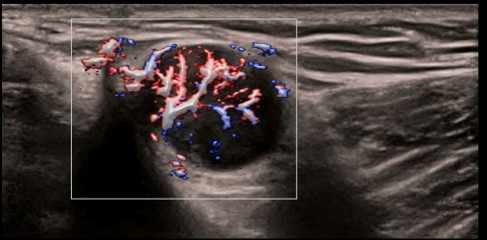

- HR Flow, Echo Boost

- V-FLOW - Živý vektorový tok krvi pre vizualizáciu komplexnej mikro hemodynamiky

CPP - Percento farebných pixelov, výpočet percentuálneho podielu farebných pixelov v rámci definovanej oblasti záujmu

CPP: Vhodné na diagnostiku extrémne jemných prietokov (napr. reumatoidná artritída). Automatická štatistika percentuálneho podielu farebných pixelov v rámci vyšetrovanej oblasti.

CPP: Vhodné na diagnostiku extrémne jemných prietokov (napr. reumatoidná artritída). Automatická štatistika percentuálneho podielu farebných pixelov v rámci vyšetrovanej oblasti.

CPP: Vhodné na diagnostiku extrémne jemných prietokov (napr. reumatoidná artritída). Automatická štatistika percentuálneho podielu farebných pixelov v rámci vyšetrovanej oblasti.